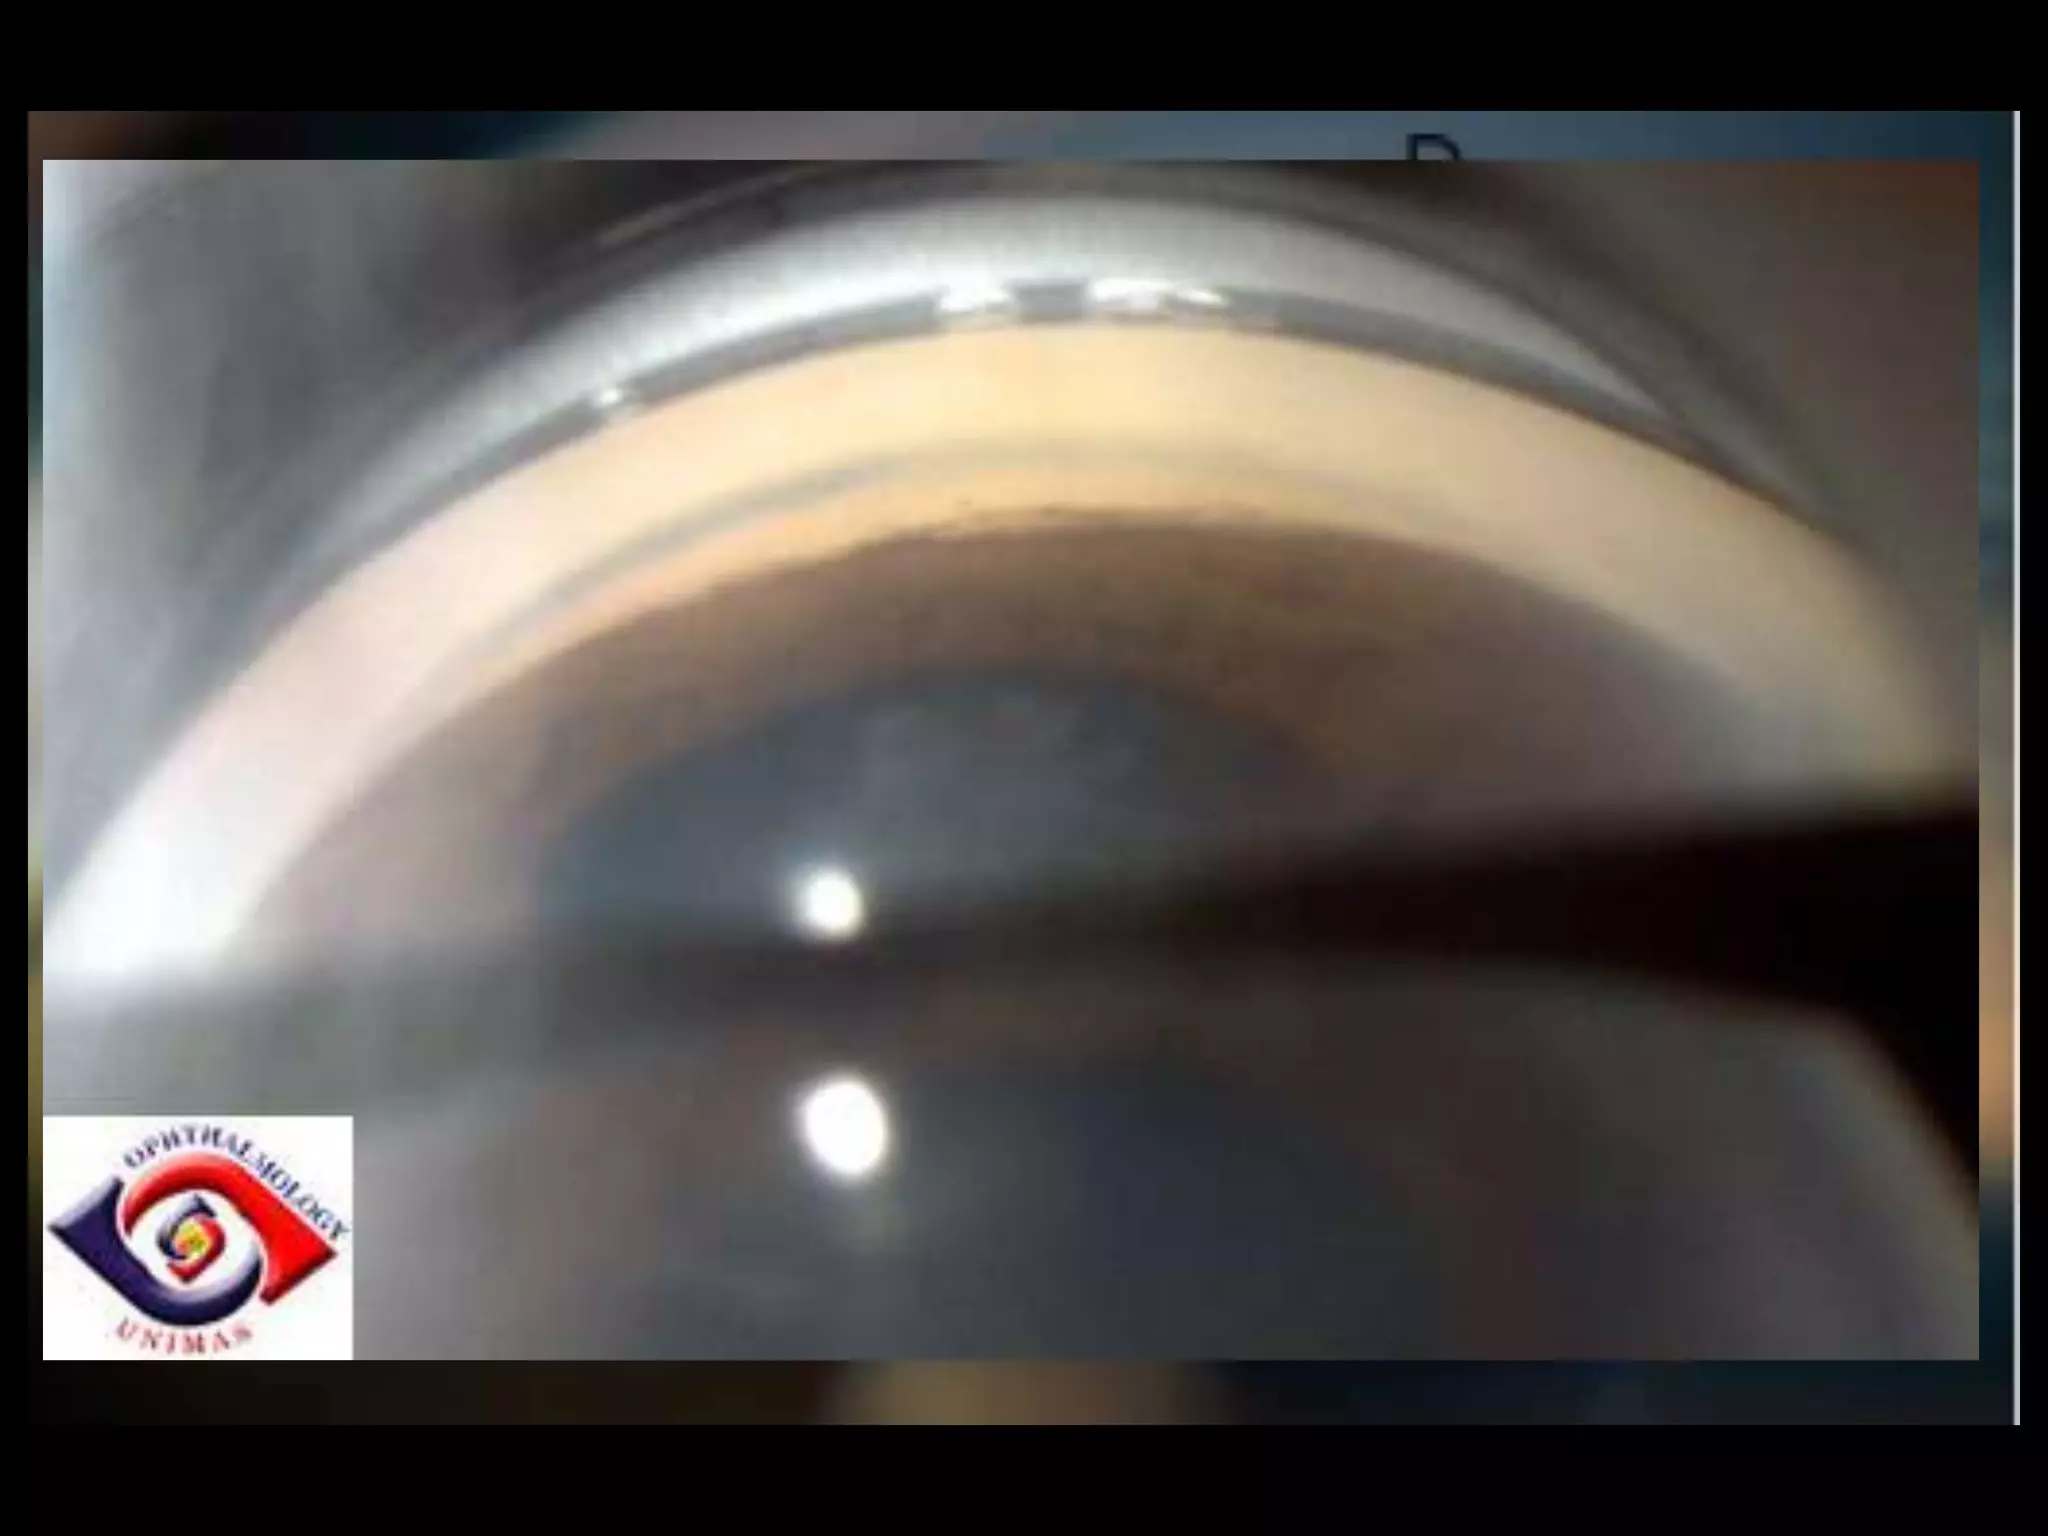

Direct gonioscopy Technique

indirect gonioscopy

Direct gonioscopy Technique indirect gonioscopy